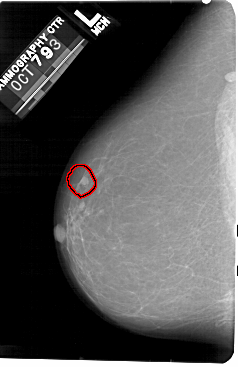

A_1476_1.RIGHT_MLO

RIGHT_CC LINES 5491 PIXELS_PER_LINE 3421 BITS_PER_PIXEL 12 RESOLUTION 43.5 NON_OVERLAY

FILE: A_1476_1.LEFT_CC.OVERLAY

TOTAL_ABNORMALITIES 1

ABNORMALITY 1

LESION_TYPE MASS SHAPE ROUND MARGINS CIRCUMSCRIBED

ASSESSMENT 4

SUBTLETY 4

PATHOLOGY BENIGN

TOTAL_OUTLINES 1

BOUNDARY